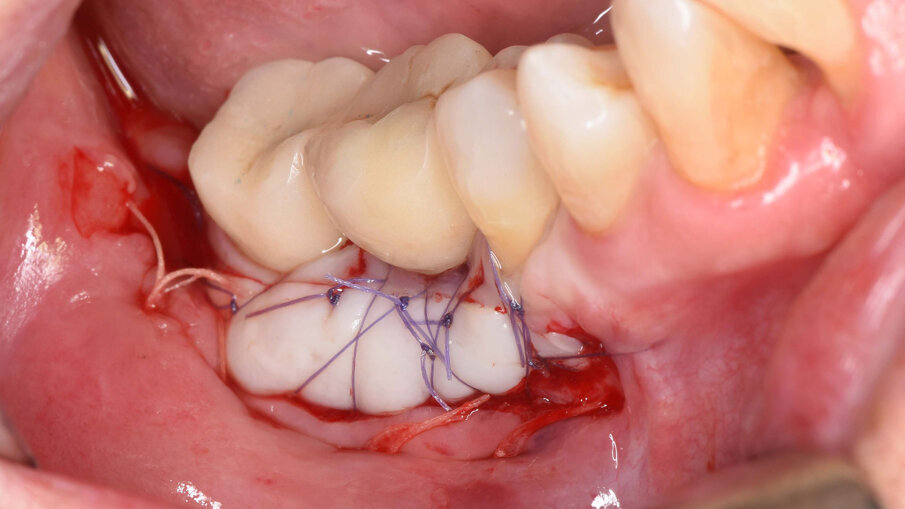

Fig. 7_Sutura ermetica del lembo di accesso mediante punti a materassaio orizzontale e punti singoli staccati, dopo l’esecuzione di rilasci periostali.